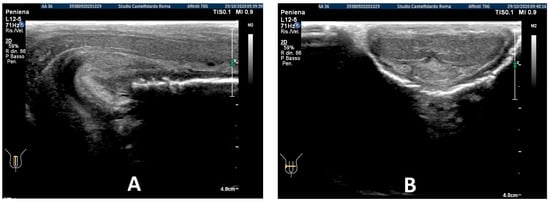

After three treatment cycles, for an overall 2 years and 5 months (29 months) of multimodal treatment, the IIEF score of the patient at follow-up was the same (scoring 26). We observed that the lateral-left penile curvature had an angle reduced to 10 degrees, similar to the curve present before PD (congenital curve). The ultrasound examination no longer showed any plaque (Figure 4).

After the completion of the third treatment cycle, and after 2 years and 9 months (33 months), the patient underwent follow-up with a physical exam and a penile Doppler ultrasound. At follow-up, the IIEF score was 28. The penile pain was no longer present. We then observed an absence of penile deformation. The ultrasound examination no longer showed any plaque (Figure 8).

Figure 4. Ultrasonography of the penis after the 3rd therapy cycle. (A) Longitudinal view; (B) axial view.

Figure 8. Ultrasonography of the penis after the 3rd therapy cycle. (A) Longitudinal view; (B) axial view.